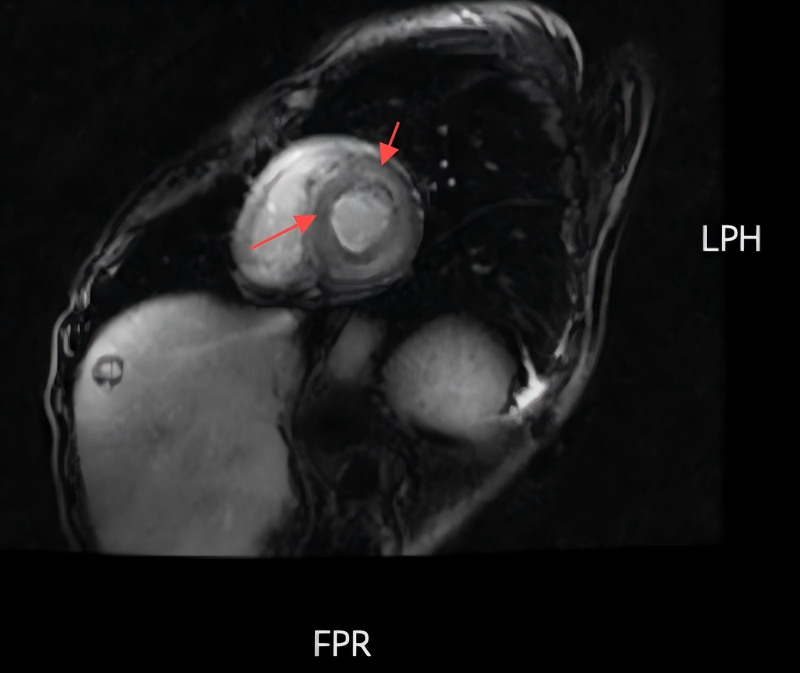

Diagnoses: Cardiac magnetic resonance imaging revealed findings indicative of AC, including left ventricular hypertrophy, diffuse delayed enhancement, and atrial enlargement. The diagnosis of immunoglobulin light chain amyloidosis was confirmed by endomyocardial biopsy, which was positive for κ light chains.